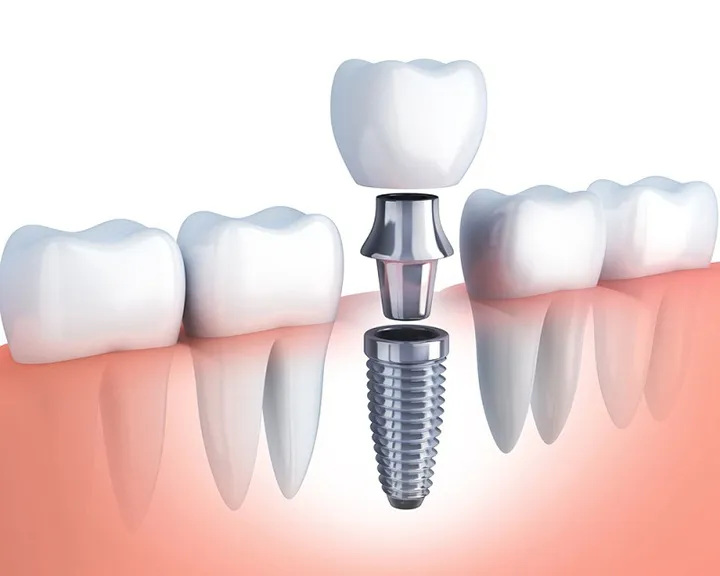

Trong một số trường hợp nặng hơn, bác sĩ nha khoa sẽ kết hợp điều trị nha chu chuyên sâu như cắm trụ, tiểu phẫu hoặc sử dụng thuốc đặc trị. Các loại thuốc thường dùng có tác dụng giảm viêm, tiêu diệt vi khuẩn gây bệnh và nâng cao khả năng kháng viêm của tổ chức nha chu.